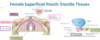

The urogenital triangle consists of what 5 things?

- Skin

- Superficial fascia

- Superficial perineal pouch

- Perineal membrane

- Deep perineal pouch

The Superficial fascia of the urogenital triangle consists of 2 layers, a fatty layer and a membranous layer known as……………….

Colle’s fascia

The superficial perenial pouch is located between the colles’s fascia and the perineal membrane. It does what?

anchors external genitalia

The deep perineal pouch is located between the pelvic diaphragm and the perineal membrane. It includes what important structure?

external urethral sphincter